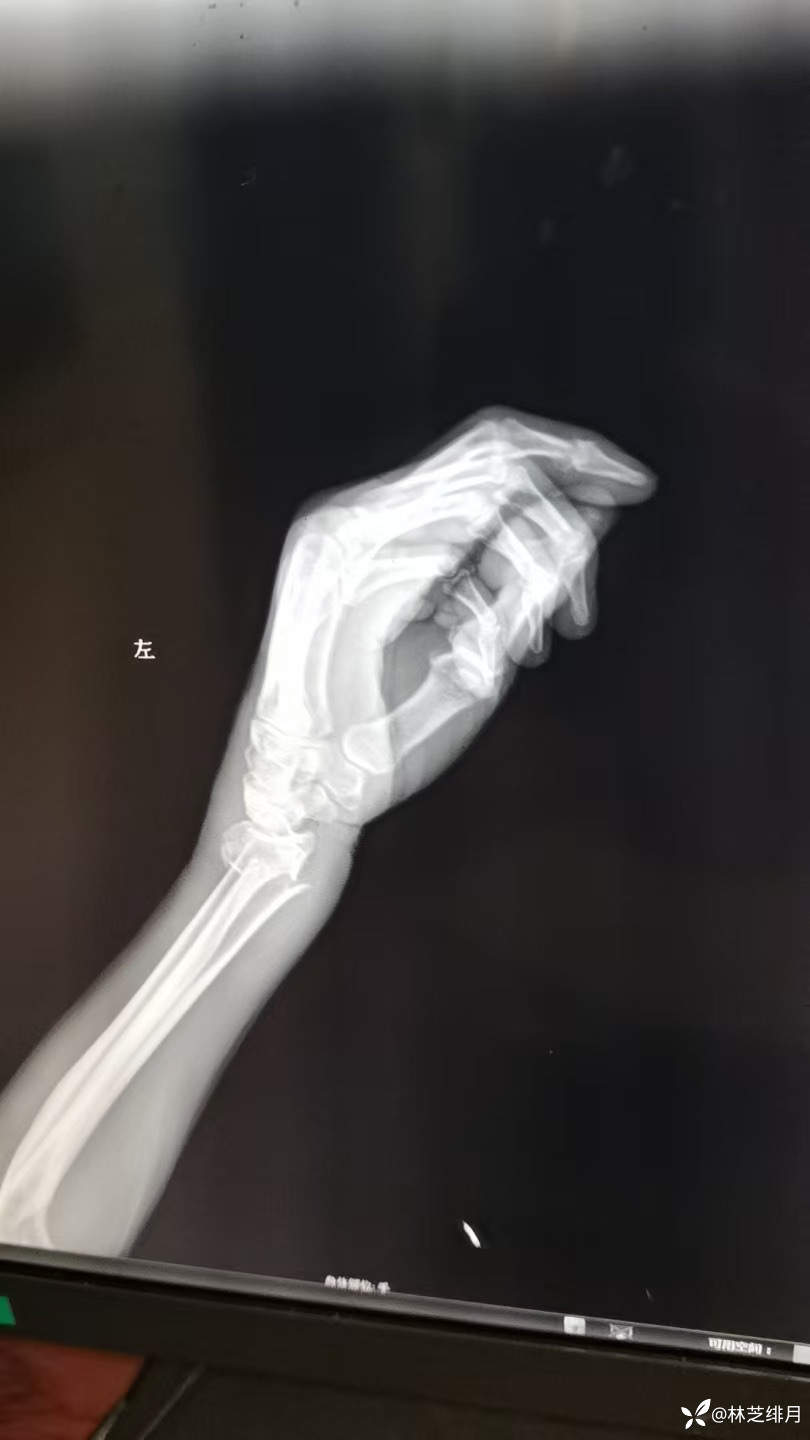

医院同时收了五个病人,有个88岁老爷子输完液准备回去,结果回去在我们医院摔了一跤,手直接肿胀畸形了。

当然得我出马,手法复位后纸板捆绑固定。

复位前的照片没有拍了。